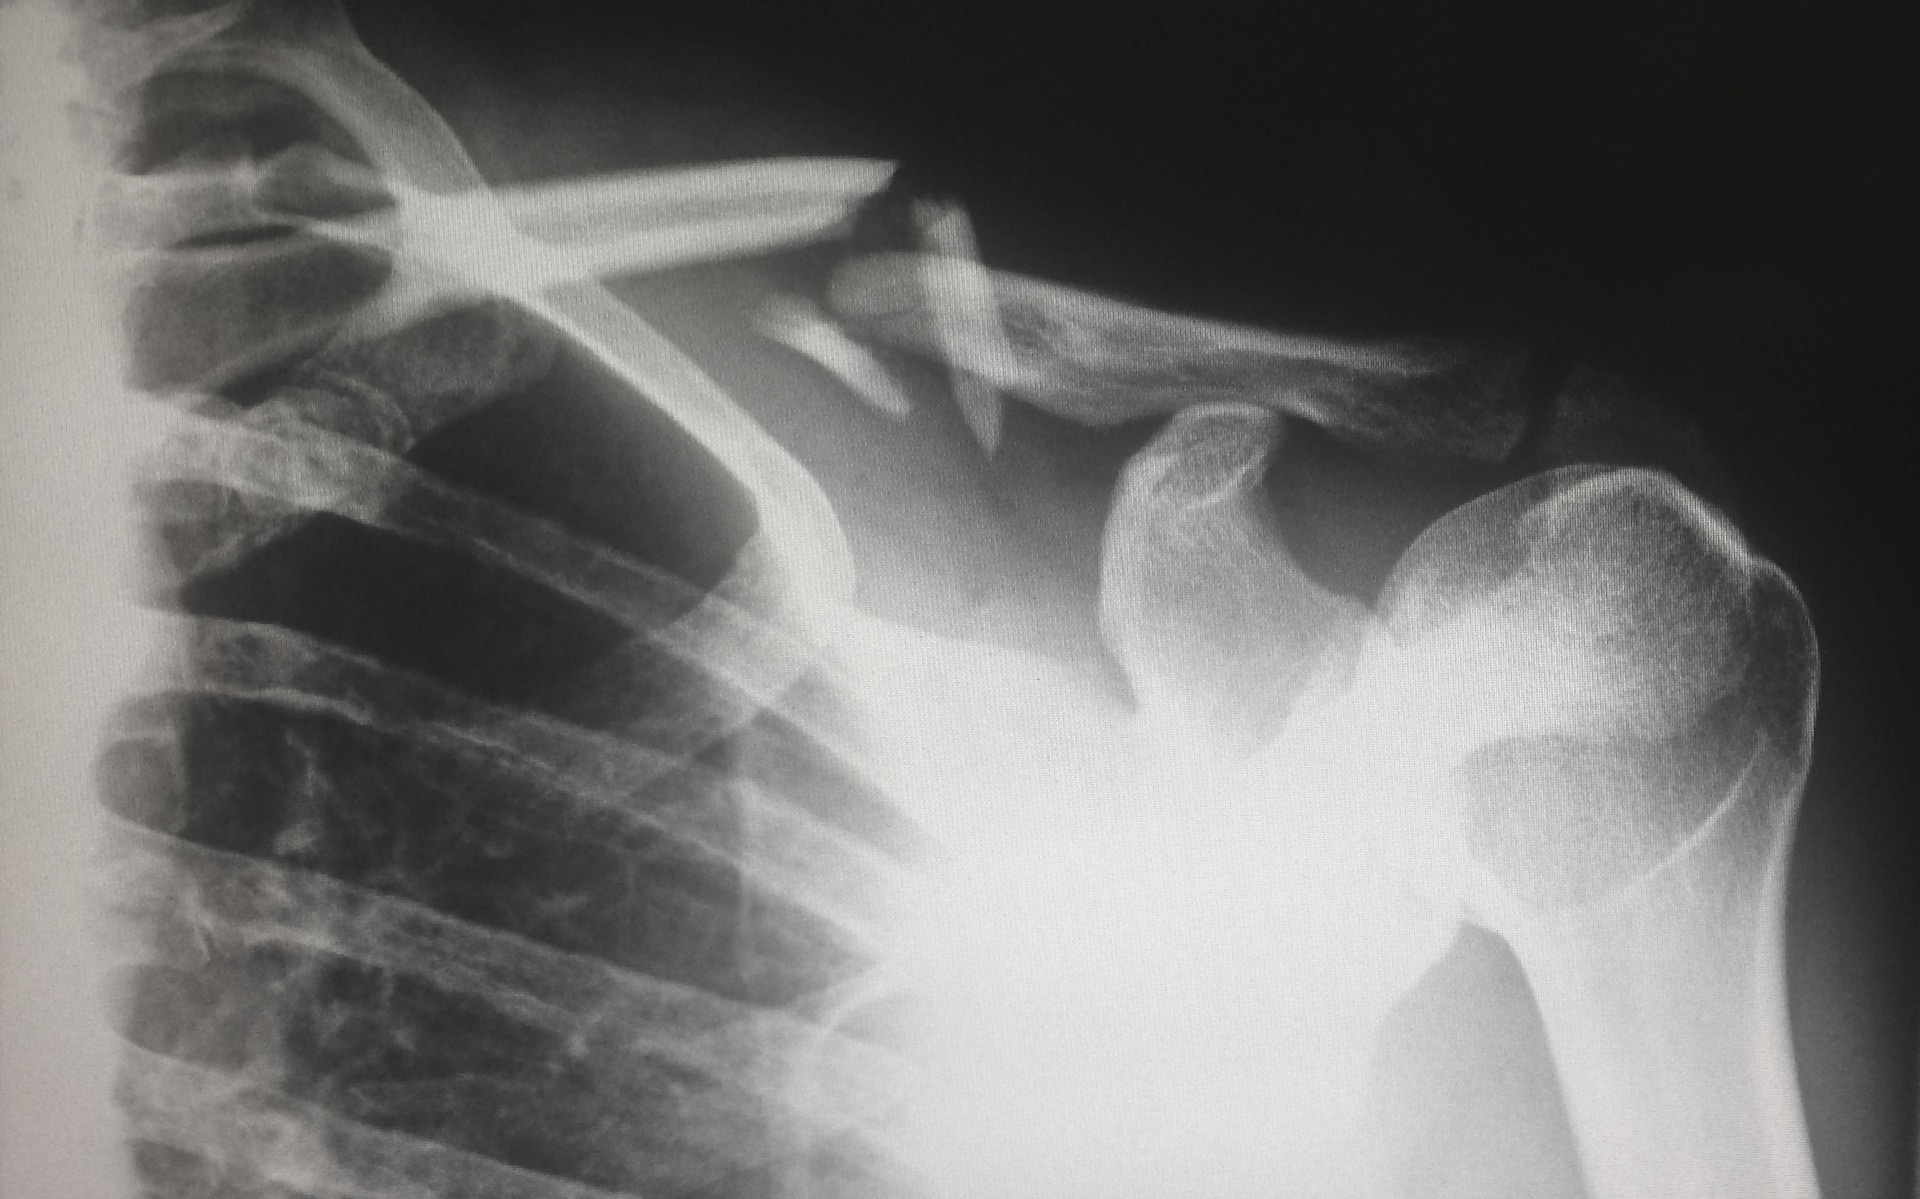

• Broken or crushed bones